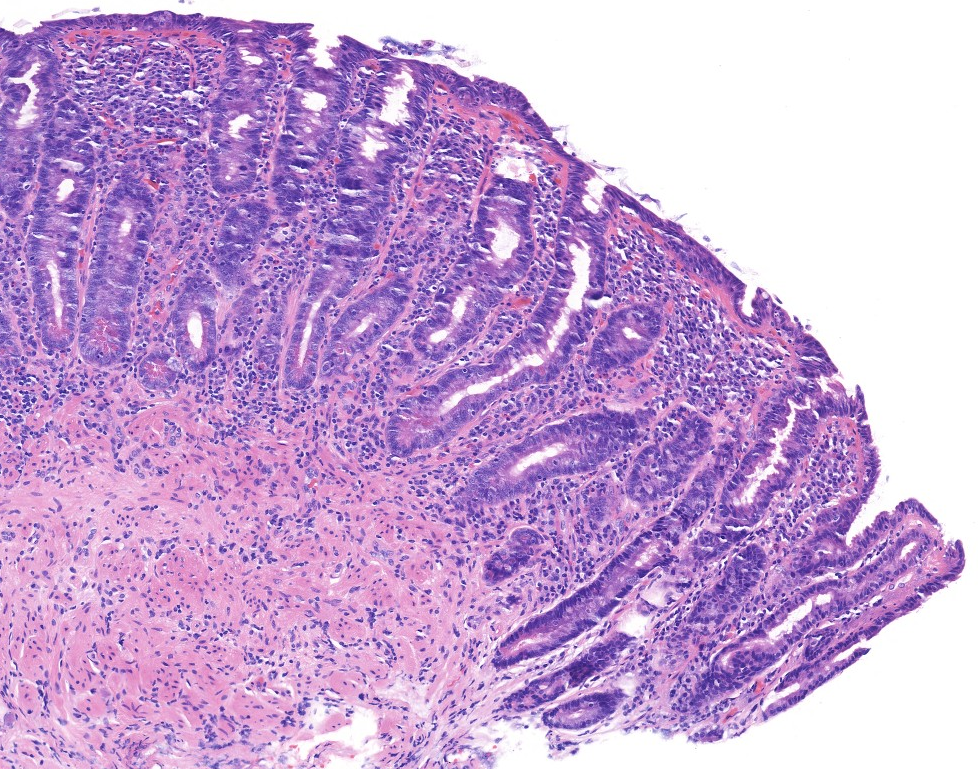

Celiac disease Histology (H&E):

Normal mucosal biopsy Histology (H&E):

Jilab has developed digital quantitative morphometry tools for celiac disease biopsy pathology, including morphometric methods for analyzing duodenal villus atrophy, crypt hyperplasia, and inflammation.

VH/CD and IEL counting using proprietary image analysis software

Villus height : Crypt depth measurement